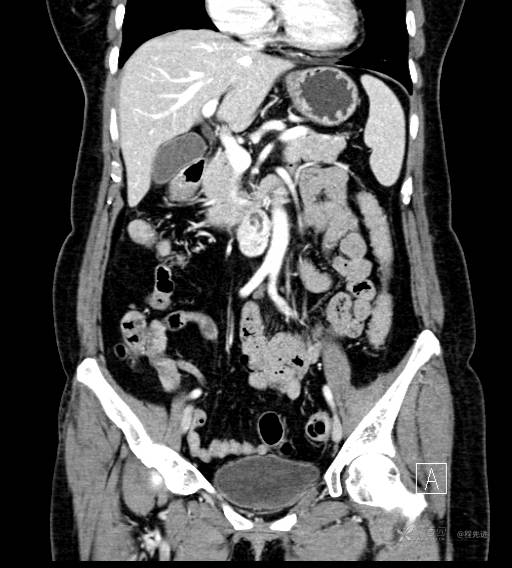

CT增强动脉期

CT增强冠状位重建